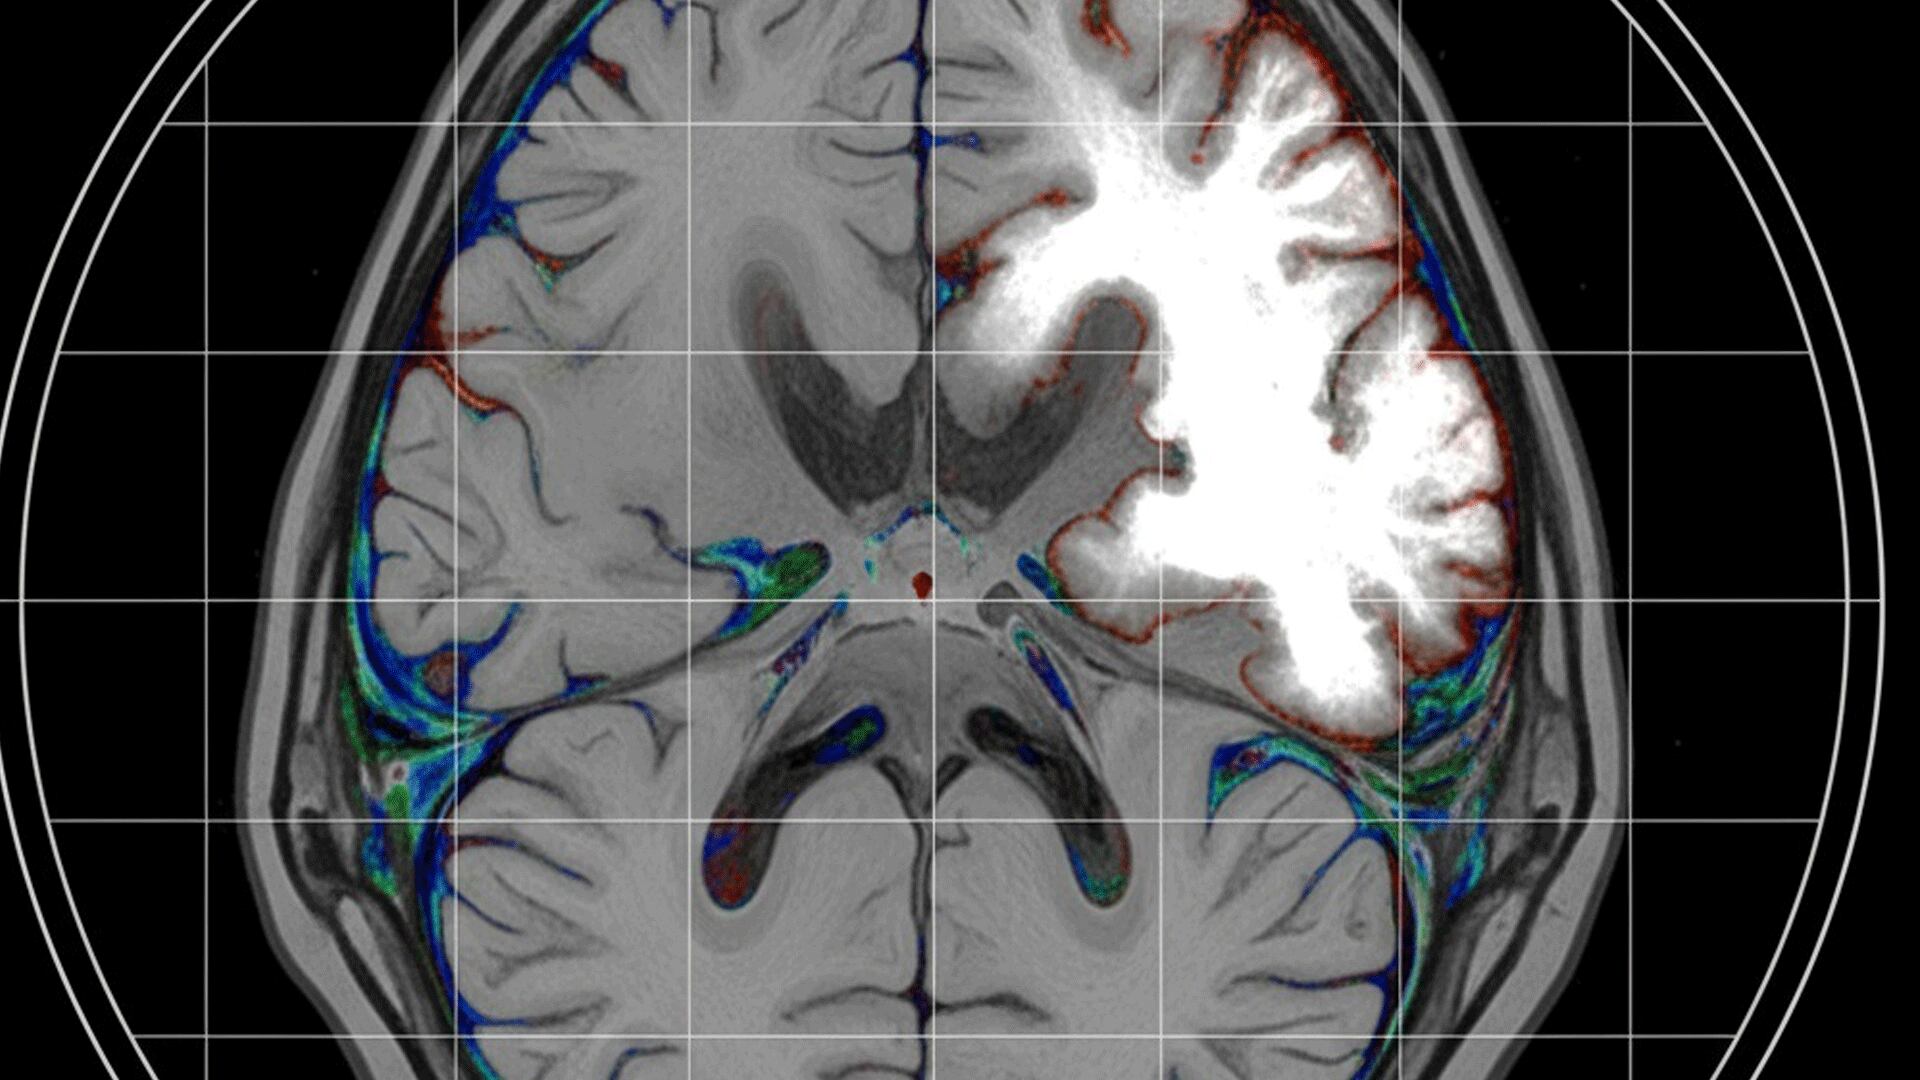

Prueba de imagen de diagnóstico de ictus